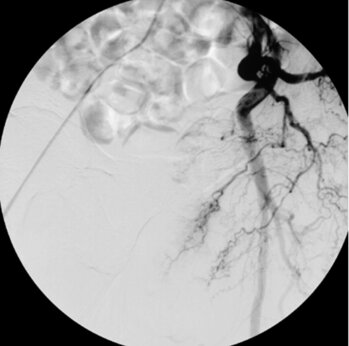

Digitale Subtraktionsangiografie: Nach Spiralembolisation der Bronchialarterie zeigt sich ein kompletter Verschluss des Gefäßes. Die Blutungen (Bluthusten) des Patienten kamen nach dem Eingriff zum Stillstand.